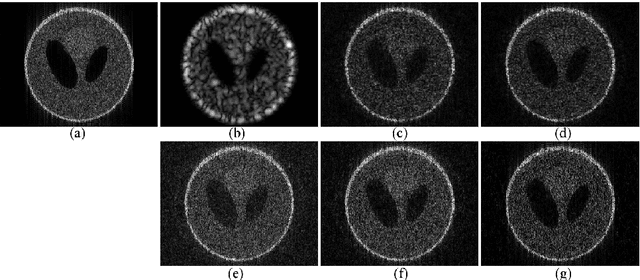

Abstract:High resolution ultrasound image reconstruction from a reduced number of measurements is of great interest in ultrasound imaging, since it could enhance both the frame rate and image resolution. Compressive deconvolution, combining compressed sensing and image deconvolution, represents an interesting possibility to consider this challenging task. The model of compressive deconvolution includes, in addition to the compressive sampling matrix, a 2D convolution operator carrying the information on the system point spread function. Through this model, the resolution of reconstructed ultrasound images from compressed measurements mainly depends on three aspects: the acquisition setup, i.e. the incoherence of the sampling matrix, the image regularization, i.e. the sparsity prior, and the optimization technique. In this paper, we mainly focused on the last two aspects. We proposed a novel simultaneous direction method of multipliers-based optimization scheme to invert the linear model, including two regularization terms expressing the sparsity of the RF images in a given basis and the generalized Gaussian statistical assumption on tissue reflectivity functions. The performance of the method is evaluated on both simulated and in vivo data.

Abstract:The interest of compressive sampling in ultrasound imaging has been recently extensively evaluated by several research teams. Following the different application setups, it has been shown that the RF data may be reconstructed from a small number of measurements and/or using a reduced number of ultrasound pulse emissions. Nevertheless, RF image spatial resolution, contrast and signal to noise ratio are affected by the limited bandwidth of the imaging transducer and the physical phenomenon related to US wave propagation. To overcome these limitations, several deconvolution-based image processing techniques have been proposed to enhance the ultrasound images. In this paper, we propose a novel framework, named compressive deconvolution, that reconstructs enhanced RF images from compressed measurements. Exploiting an unified formulation of the direct acquisition model, combining random projections and 2D convolution with a spatially invariant point spread function, the benefit of our approach is the joint data volume reduction and image quality improvement. The proposed optimization method, based on the Alternating Direction Method of Multipliers, is evaluated on both simulated and in vivo data.